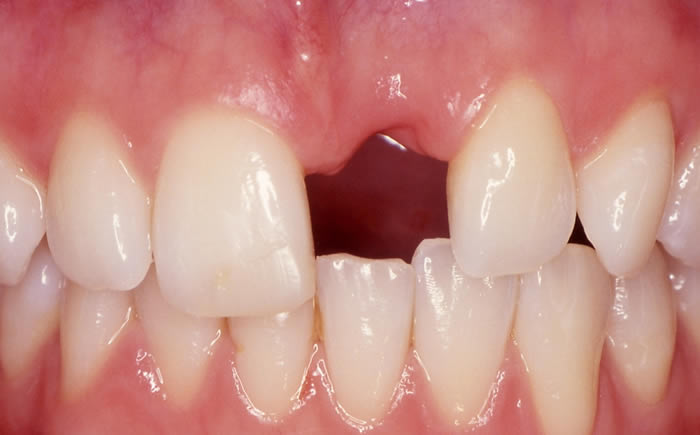

Front teeth replaced by dental implants

Case One (5 images)

Dental implants used to replace two upper front teeth